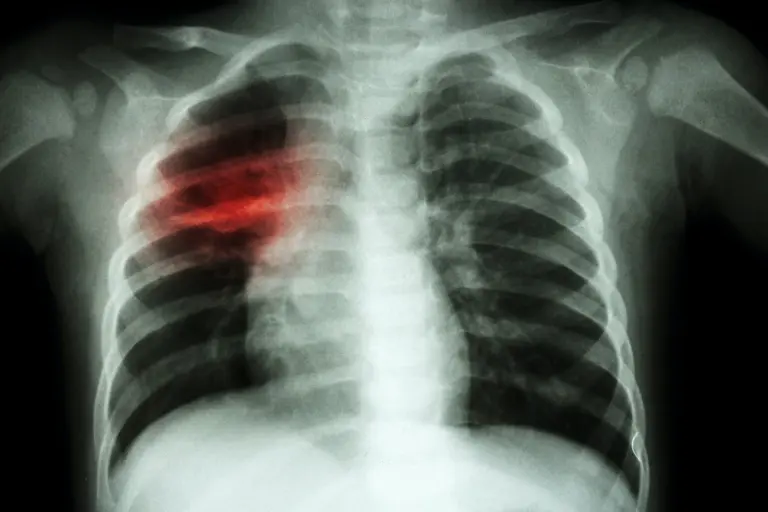

Foto: Shutterstock / Puwadol Jaturawutthichai